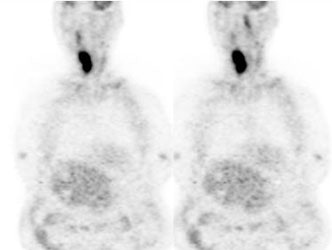

Large laryngeal cancer: The patient shown below had a large laryngeal cancer (white arrows). The PET exam demonstrated very prominent uptake within the mass, but no evidence of metastatic disease.

Large laryngeal cancer: The patient shown below had a large laryngeal cancer (white arrows). The PET exam demonstrated very prominent uptake within the mass, but no evidence of metastatic disease. |